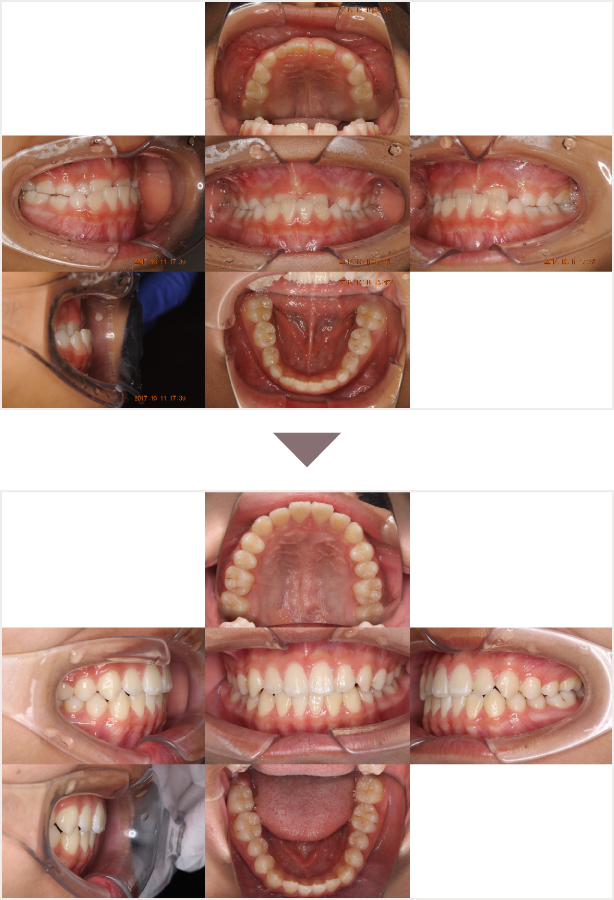

症例叢生

性別

期間6年5ヶ月

治療内容N-Bimler装置、Neo-Capを使用して治療

治療における

副作用・リスク

装着しないと効果は出ません

金額ビムラー装置:550,000円

ネオキャップ:4本

合計:572,000円